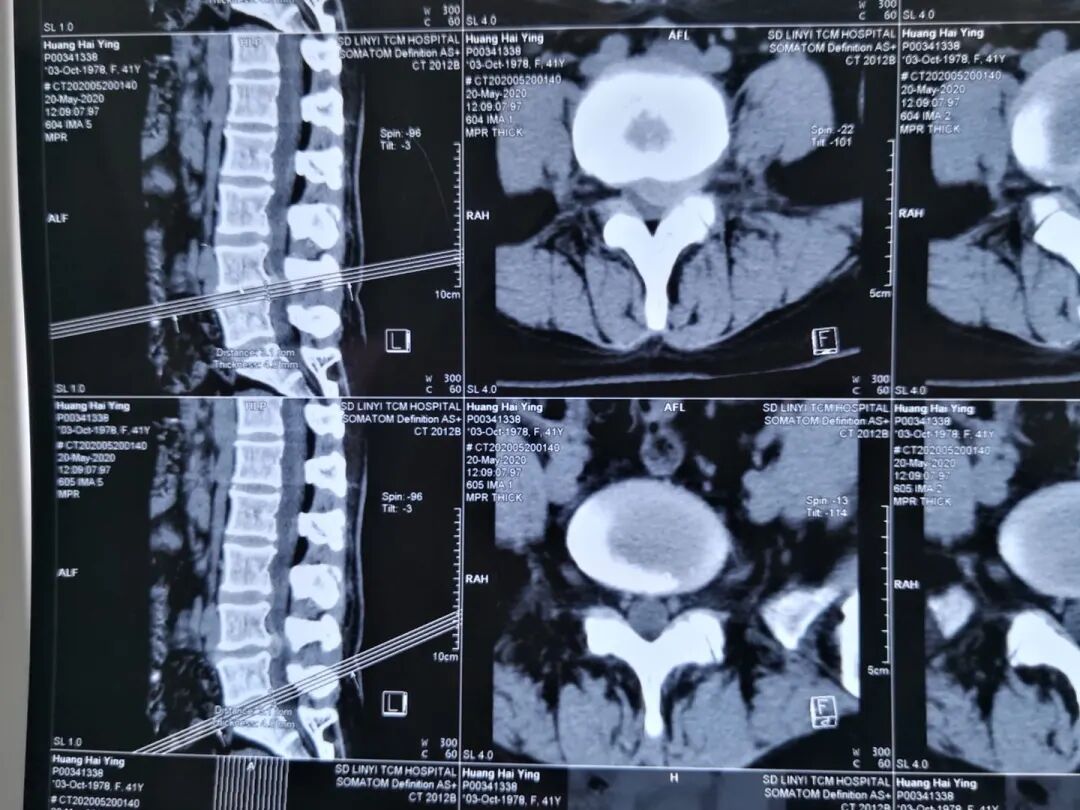

图4:术前CT

图5:术后CT